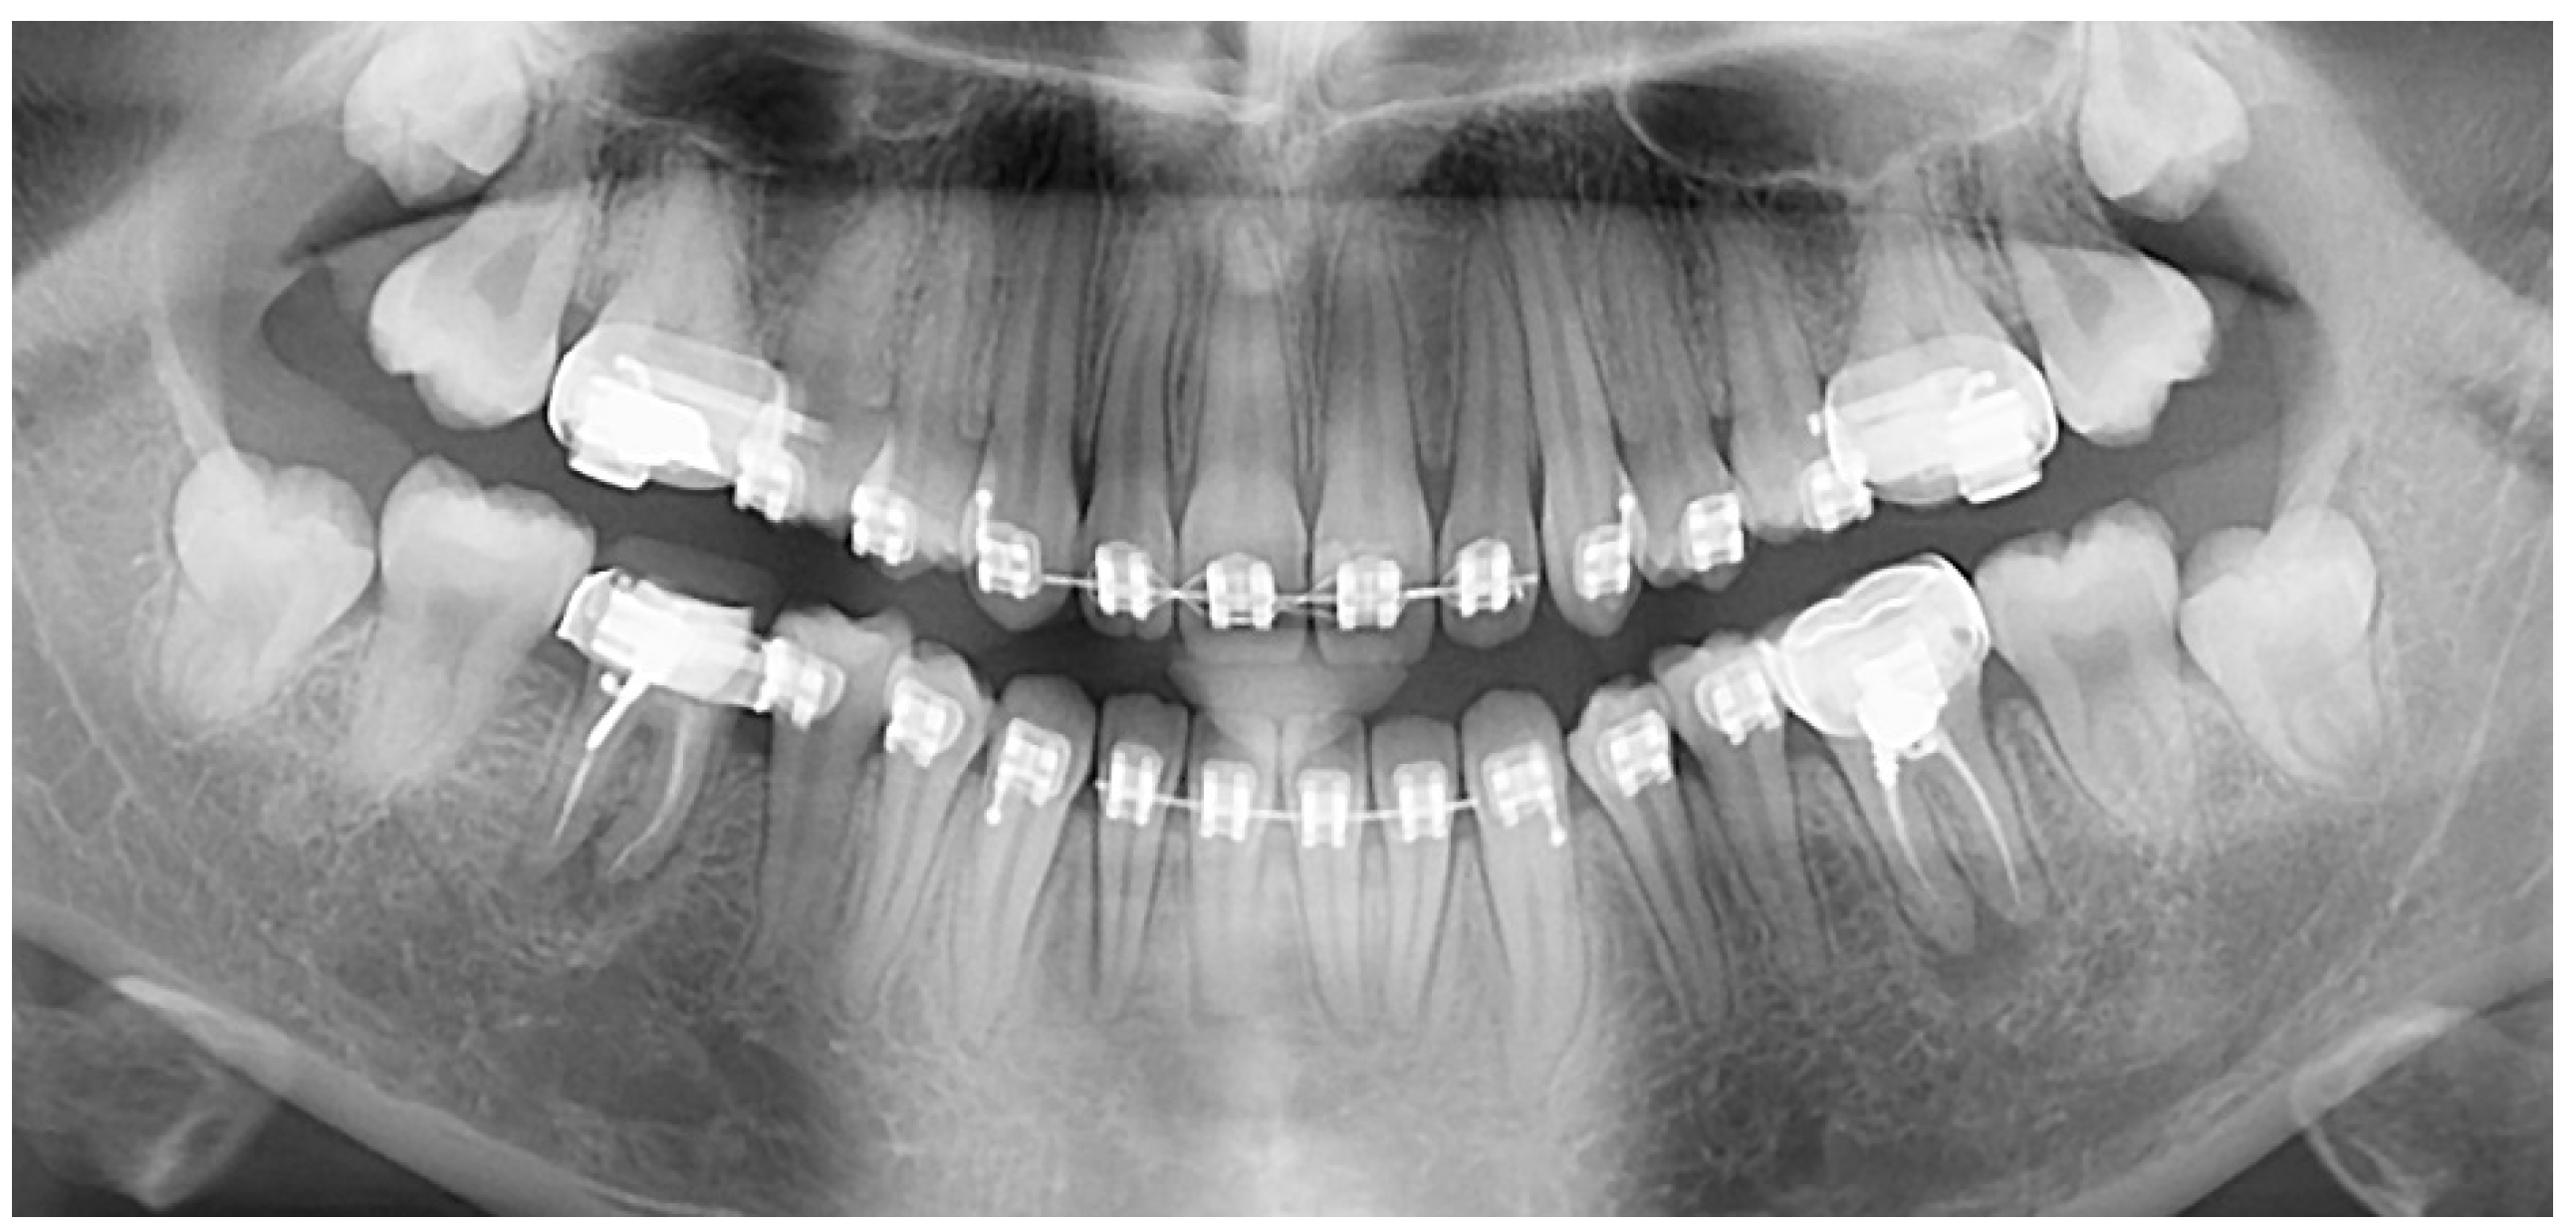

This highly frequent anomaly is of interest to numerous clinical, basic science, and public health fields [36]. The abnormal root canals in taurodont teeth is both in terms of shape and the number of encounters with complete filling of the root canal system [16]. The complex anatomy of the roots poses a challenge for a complete filling of the root canal system [7] (Figure 4). Thus, vital pulpotomy may be a suitable alternative to pulpectomy in severe cases of hypertaurodont teeth [5], a solution to be seriously considered. In the deciduous dentition, when pulp has a large extent, pulpotomy itself is not easy to perform. The extraction of a taurodont tooth is usually complicated because of a shift in the furcation area down to the apical third with the roots turning shorter and thinner. An apically placed furcation in the alveolar bone is the apparent preferred periodontal approach [7]. However, this specific different morphology may well affect the gingival line, relative to the neighboring normal teeth. Such an irregular gingival line may create difficulties in maintaining oral hygiene and cause gingival inflammation and a risk for periodontal breakdown, which may be a challenge to solve. The taurodont teeth occupy a smaller space in the alveolar bone, which may affect their stability compared to a normal tooth following their reduced ability to withstand normal occlusal wear forces [14,36]. This raises a question regarding their ability to maintain a functional passive eruption as compensation [37]. Stability should be considered when such a tooth is used as an abutment for either prosthetic or orthodontic purposes [7,16]. During orthodontic treatment, special attention must be given to the orthodontic force application due to the reduced alveolar bone support and risk factors for induced inflammatory root resorption of the shortened roots [38]. An alternative treatment of clear aligners is a viable option over the fixed appliances based on their effectiveness in shortening treatment duration [39] combined with superior periodontal health [40].

Figure 4.

Clinical challenges that taurodont teeth posed for the general practitioner.